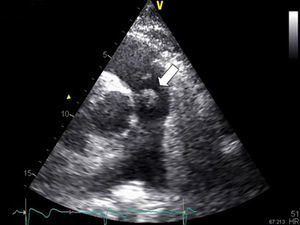

Case reportA 68-year-old man, diabetic with peripheral neuropathy, was admitted to the Internal Medicine ward due to prolonged fever. He reported suffering from both asthenia and fever over the preceding three weeks. He had been given empirical amoxicillin plus clavulanic acid two weeks previously, a treatment that led to transient symptomatic improvement. During initial observation the patient was normotensive with an axillary temperature of 37.6°C. Both cardiac and pulmonary examinations were normal. His right hallux exhibited a lesion, which by his account had been present for the preceding twelve months (Figure 1). Blood tests revealed leukocytosis – 22.70×109/l with 95.8% neutrophils – and elevated CRP (2.14mg/dl). PA chest X-rays were normal. Blood cultures revealed methicillin-susceptible Staphylococcus aureus (MSSA). Transthoracic echocardiography (TTE), and later transesophageal echocardiography (TEE), both revealed a mobile, ovoid, 1-cm diameter mass adhering to the arterial face of the pulmonary valve, and another highly mobile filiform mass also adhering to the PV and protruding into the right ventricle (Figures 2 and 3) without causing any obstruction. Taking into account the antibiotic susceptibility test results, the prescribed antibiotic therapy consisted of flucloxacillin 1000mg IV every 4h and gentamicin 1mg/kg every 8h for six weeks. The fever began to subside on the eighth day. Control echocardiography during hospitalization showed only mild to moderate pulmonary regurgitation. The patient had no other clinical manifestations or identifiable complications, including thromboembolism. Blood cultures were negative after the antibiotic course was completed. The patient was discharged home after six weeks. Nevertheless, the pre-discharge echocardiogram revealed persistence of the vegetations (Figure 4), which had developed a fibrotic appearance, and persistent mild to moderate pulmonary regurgitation.